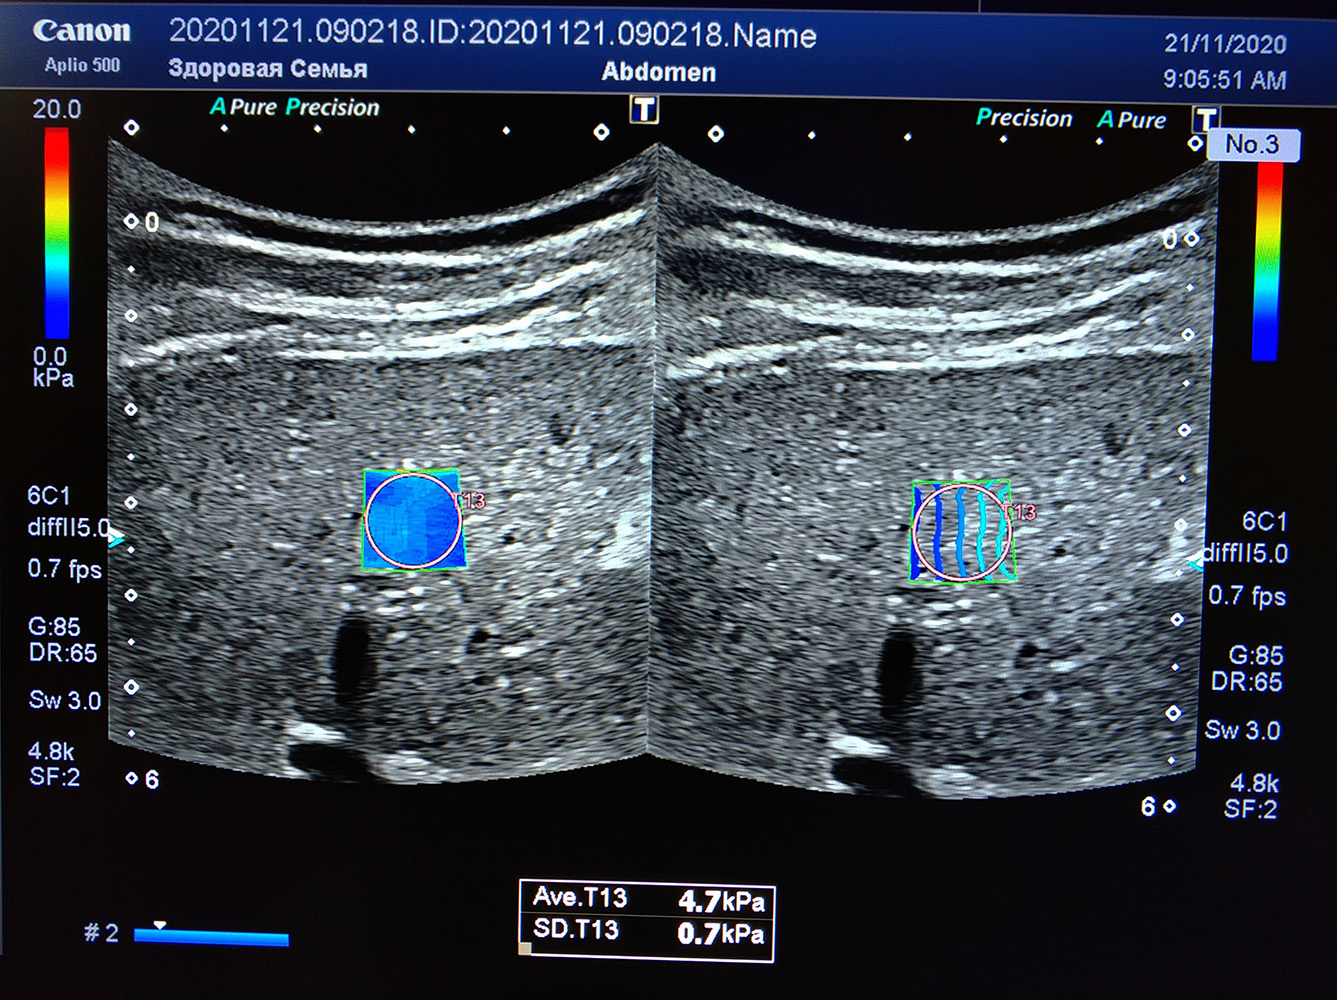

Aplio 500 значительно упрощает работу путем создания специальной карты отображения сдвигов поперечных волн. Выглядит это как окно, заполненное цветными линиями. В случае приближения плотной структуры к полю исследования или прилегания крупного сосуда, результаты будут не достоверными. Такое НЕ оптимальное ЭХО окно будет неизбежно препятствовать исследованию. Именно на эти проблемы и реагируют линии, отображающие сдвиг. Чем линии прямее – тем качественнее будет результат. Таким образом, вы не только сразу видите качество ЭХО окна и места измерений, но и можете выбрать наиболее оптимальные участки в поле.

Однако карта там не одна, в режиме двух экранов мы видим и вторую карту – разметку скорости сдвиговых волн, из которых сразу можно автоматически пересчитать плотность в килопаскалях. Синие цвета – мягкие участки, красная расцветка говорит о выраженной плотности. Измерение проводится по участку с равномерной окраской, это позволяет избегать артефактов и мелких связок. Качество проведенного исследования резко возрастает.

Система отчета эластографии печени позволяет отобразить все 13 точек измерения, указать глубину, скорость распространения, количество килопаскаль и прочие необходимые данные в единой таблице также, как это делает эталонное оборудование для этого метода – фиброскан. Расчет медианы и межквартального интервала система производит автоматически. Такую таблицу можно распечатать сразу с прибора и не тратить время на внесение вручную в карту каждой цифры.